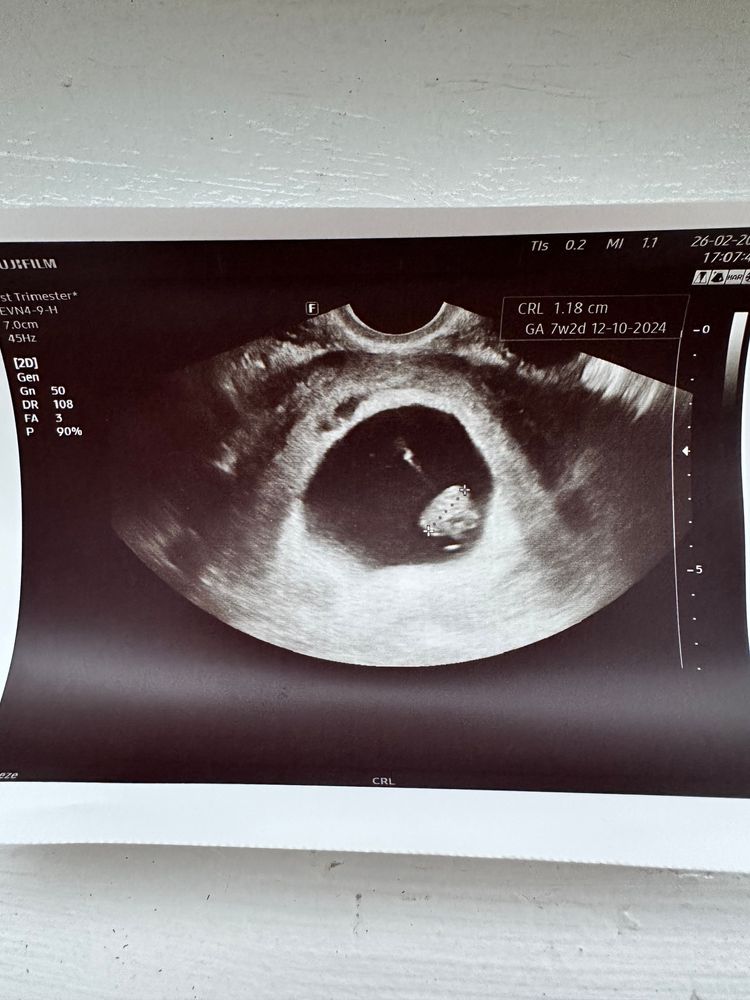

Zelenka, дело в том,что этот гинеколог мне даже выписку с узи не дал,ничего не сказал,сказал просто что всё хорошо и дал снимок с узи Изображение

Натик, я просто не понимаю там один сантиметр ктр или это один миллиметр

Катерина, у вас 1 см 17 мм по фото.

Натик, тогда точно должно быть слышно сердечко 😭

Милена, здравствуй,если я правильно поняла то 1.17 Изображение

Marime, нет, у меня эмбриончик есть,но да ,я не хочу так просто сдаваться и идти на выскабливание🥺хочу точно знать что с малышом Изображение